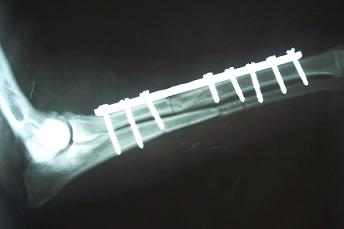

Καλά πήγε η εγχείρηση, καλή και η ακτινογραφία αλλά έχεις ξεχάσει μέσα μια τσουγκράνα...

Τρεις τουλάχιστον ανά καταγματικο τμήμα.Καλά πήγε η εγχείρηση, καλή και η ακτινογραφία αλλά έχεις ξεχάσει μέσα μια τσουγκράνα...

Πέρα από τη πλάκα τόσες βίδες μπαίνουν στη λάμα?